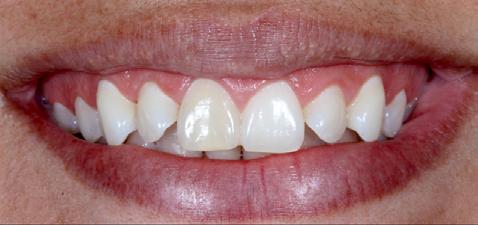

Restoring incisal wear and closing diastema with G-aenial A’CHORD. Courtesy of: Dr Aleksandra Slacan, Poland

Reshaping of teeth and diastema closure with G-aenial A’CHORD. Courtesy of: Dr Andres Silva, Spain